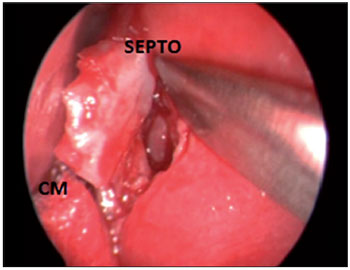

CASE STUDY #2A 35-year-old female patient sought advice from the Specialized Service in Otolaryngology in August 2010, complaining of a localized headache, cacosmia, and nasal obstruction with progressive worsening of her symptoms during the previous 6 months. Her symptoms had remained after drug treatment with amoxicillin and clavulanate potassium for 10 days. Video-endoscopy showed a deviated septum and inferior turbinate hypertrophy. A CT scan of the paranasal sinuses and nasal cavity in the axial, coronal, and sagittal planes with a bone window of 2500-3500 rads was requested, which identified pneumatization of the crista galli apophysis with signs of mucosal thickening and obliteration interiorly. We introduced antibiotic treatment (levofloxacin at a dose of 500 mg/day) for 14 days, corticosteroids (prednisone at a dose of 40 mg/day) for 7 days, and symptomatic analgesia. The patient's symptoms improved temporarily, but 5 days after treatment with antibiotics was stopped, recurrence of her symptoms occurred. A second CT scan of the paranasal sinuses and nasal cavity showed the maintenance of mucosal thickening and obliteration within the crista galli (Figure 3). Endoscopic surgery by a transseptal approach through the right nostril was indicated for drainage and cleaning of the pneumatized crista galli (Figures 4-7).

FFigure 6. Intraoperative endoscopic visualization of the right nasal cavity showing transseptal opening of the bone wall of the pneumatized crista galli.

SEPTO = nasal septum; CM = middle turbinate.